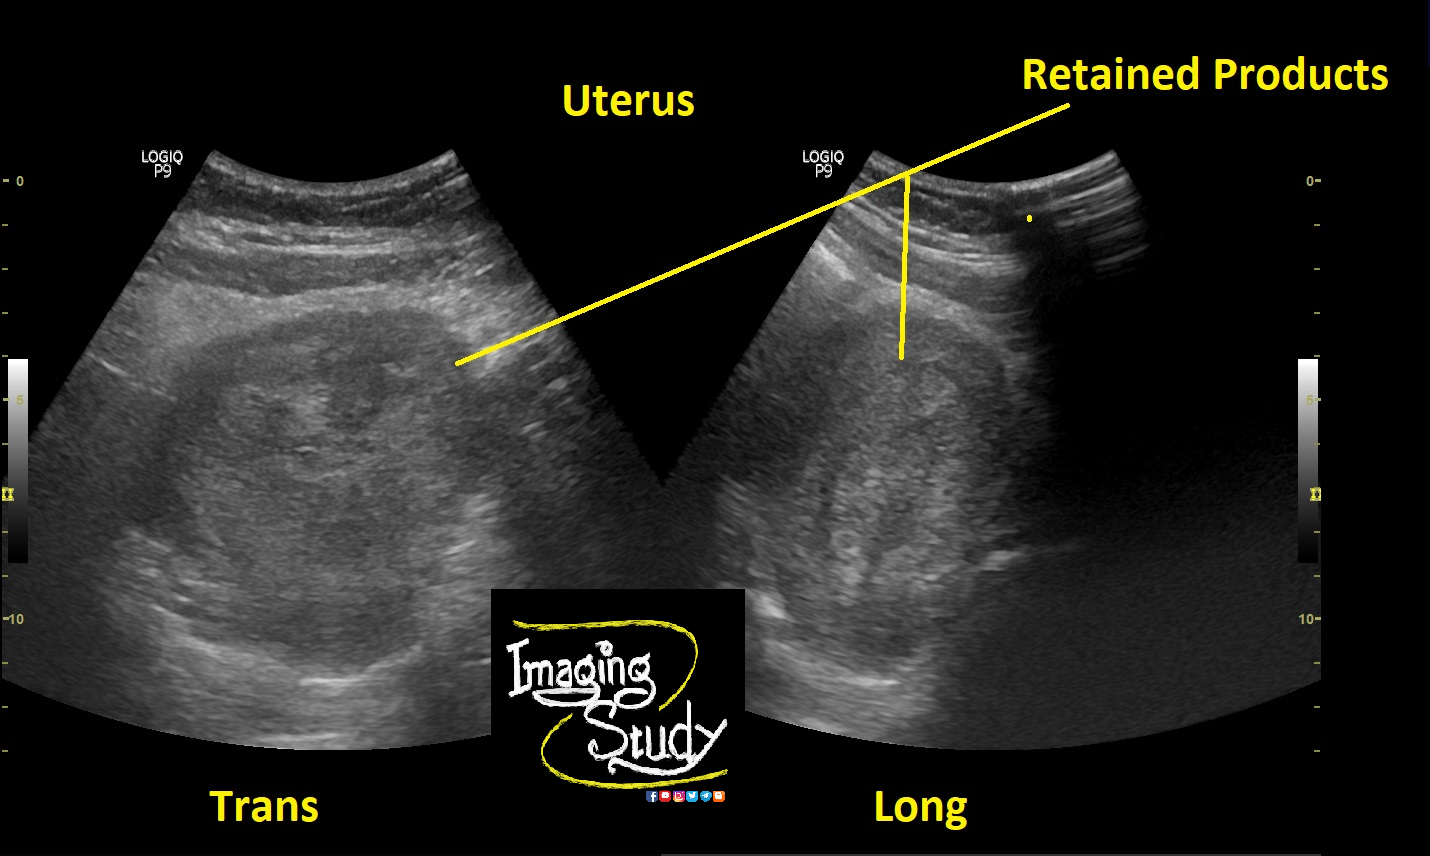

Incomplete Abortion

• Products of conception are not completely expelled out

Ultrasound Findings:

• Irregular Mixed echogenic substances are noted within the uterine cavity

• Vascularity may be noted on Doppler if trophoblast tissue is present. Urine for PT may become positive there